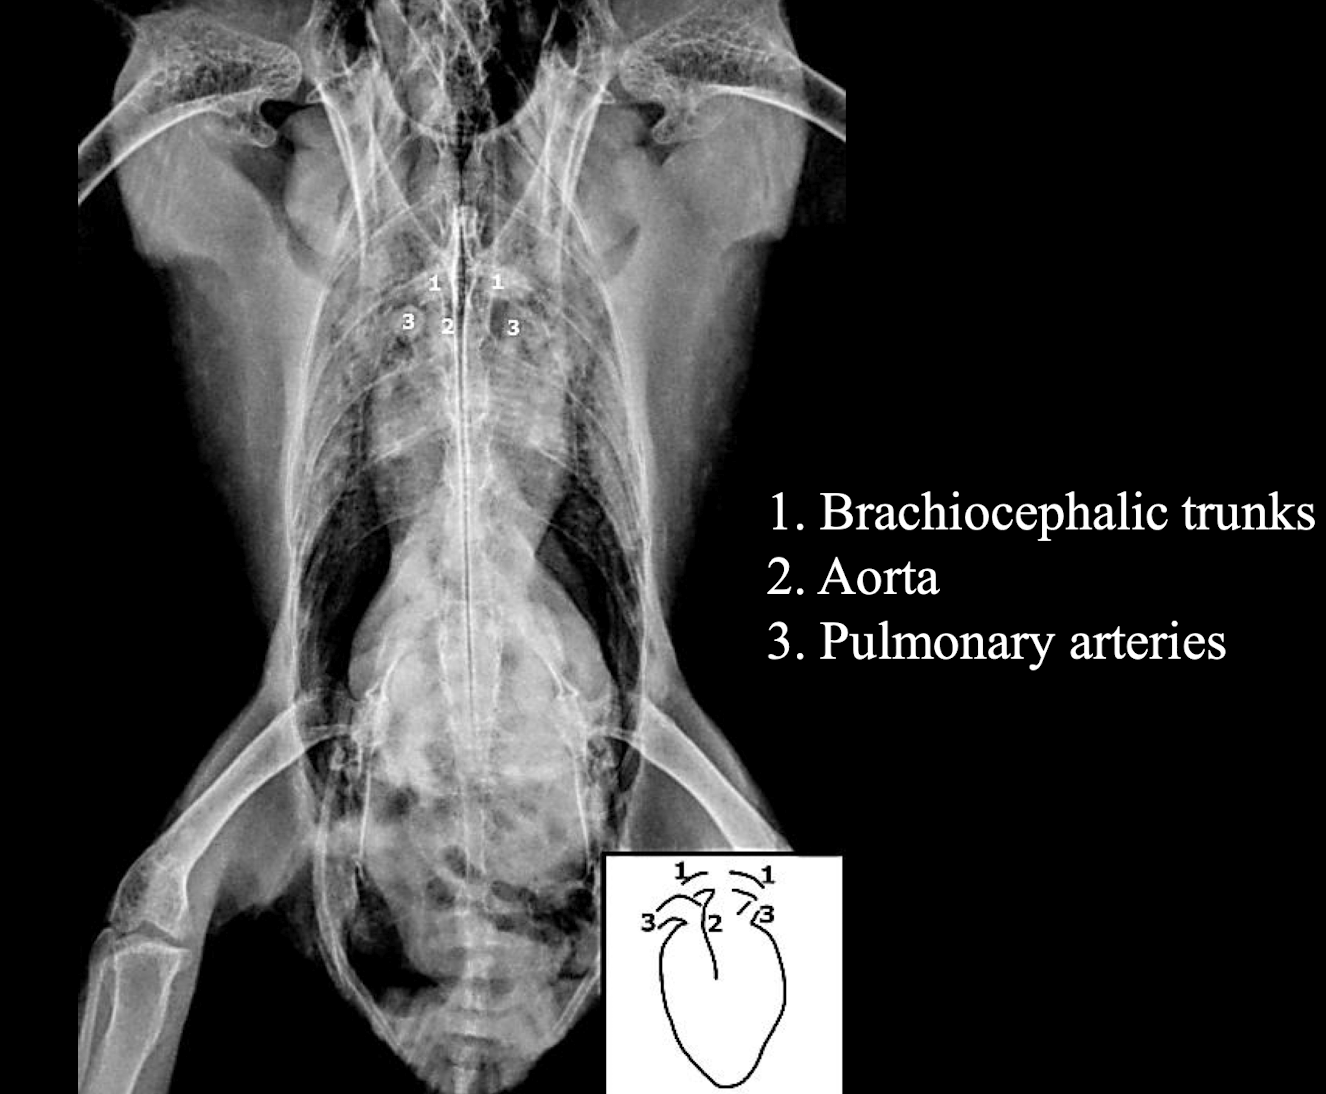

How does an avian heart's size compare to that of mammals, especially in falcons?

The heart is larger than in mammals, especially in falcons.

What is the normal heart width on a VD radiograph for psittacines and hawks?

Less than 60% of the thoracic width.

Great vessels in the heart VD

Great vessels in the heart lateral